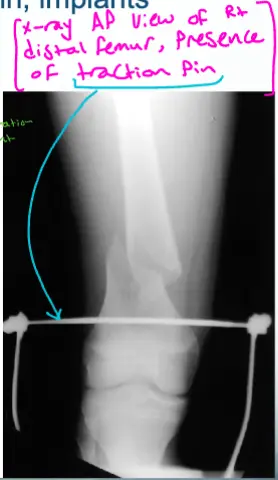

- X-ray AP view of Rt distal femur, presence of traction pin